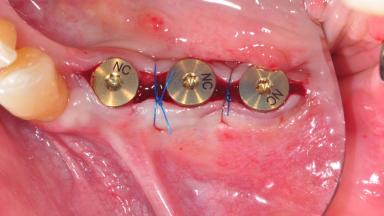

After the placement of three diameter-reduced two-piece implants the bone is augmented with autologous bone chips and DBBM particles to enlarge the crest volume. The surgery is completed with the application of two membrane layers and primary wound closure.

Bone Augmentation Horizontal|Simultaneous

Augmentation Materials Autogenous chips|Xenogenous|Membrane